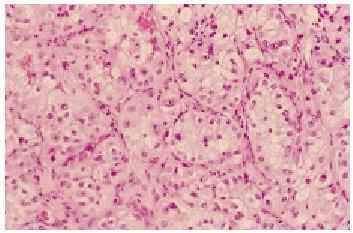

Fig. 4.--En la biopsia cutánea se observaba en dermis profunda una infiltración por un carcinoma de células claras. El tumor se disponía en nidos sólidos separados por finos septos de estroma vascularizada.

Fig. 5.--Las células presentaban un citoplasma claro y vacuolado y núcleos vesiculosos con macronucléolos.